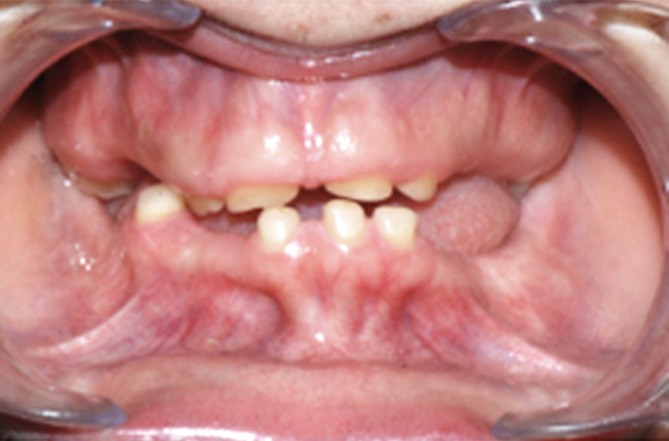

Le rôle de dépistage du chirurgien-dentiste est central dans les différents types d’anomalies du développement dentaire isolées ou syndromiques, comme les agénésies dentaires multiples, les anomalies de structure ou de morphologie. De nombreux syndromes polymalformatifs associent un phénotype dentaire à diverses atteintes systémiques, parmi lesquels on retrouve les dysplasies ectodermiques, les polyposes adénomateuses familiales, le syndrome ERS (Enamel-Renal syndrome), par exemple. Des signes cliniques dento-maxillaires sont retrouvés en association avec des formes de cancer cutané ou de tumeurs des systèmes nerveux ou endocrinien, citons par exemple la néoplasie endocrine multiple 2B ou le syndrome de Gorlin. Ces anomalies dentaires constituent autant de signes d’appel pour le praticien, permettant de suspecter des pathologies potentiellement sévères.

Les maladies rares, définies par une prévalence inférieure à 1/2000, sont au nombre de 9 000 et pour la grande majorité d’origine génétique (1). Une expression clinique bucco-dentaire est retrouvée dans plus de 900 de ces pathologies, par exemple dans le cadre de nombreux syndromes polymalformatifs caractérisés par un phénotype dento-facial. Des pathologies potentiellement sévères, touchant tous les systèmes (neurologique, squelettique, cutané, sensoriel) peuvent présenter des signes diagnostiques bucco-dentaires et donc être dépistées précocement par le chirurgien-dentiste.

Les signes diagnostiques, tableaux cliniques et radiologiques des pathologies illustrant au mieux ce rôle de dépistage précoce du chirurgien-dentiste sont décrits dans ce travail. Pour des raisons didactiques, nous avons classifié ces pathologies en fonction des atteintes associées, qu’elles soient ectodermiques, cancéreuses, rénales ou sensorielles. Les principales anomalies du développement dentaire (agénésies dentaires, anomalies de morphologie ou de structure des tissus minéralisés) sont décrites, en insistant sur leurs associations avec des atteintes extra-orales. Le rôle de dépistage précoce apparaît central, notamment dans les pathologies avec un risque carcinologique ou des anomalies métaboliques, pouvant engager le pronostic vital. Le chirurgien-dentiste peut être le premier professionnel de santé à diagnostiquer certaines pathologies, les signes dentaires précédant les signes généraux, comme dans la polypose adénomateuse familiale par exemple. Ce dépistage a un intérêt aussi bien diagnostique que thérapeutique, car il permettra la mise en place d’une prise en charge précoce et la préservation du capital dentaire.

Dépistage des hypo-oligodonties isolées et syndromiques

Les formes d’hypo-oligodontie isolées et syndromiques peuvent être dépistées précocement par le chirurgien-dentiste, avec toutefois des implications diagnostiques…